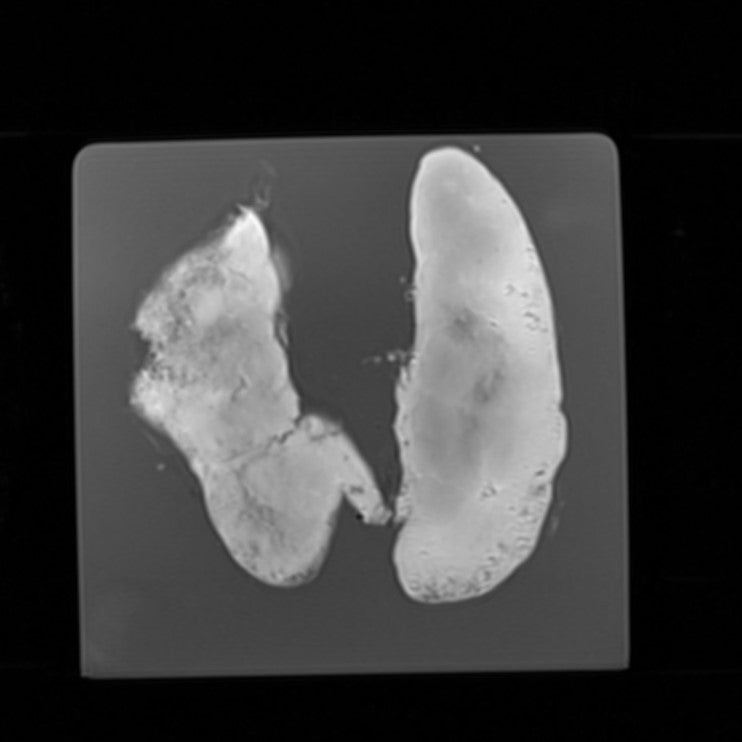

Thyroid - Normal

Radiopath – Thyroid